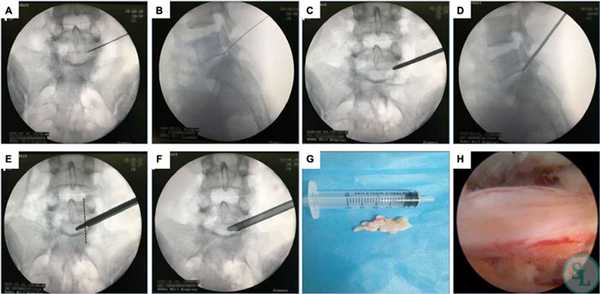

Суть операции заключается в следующем:

- Кожные покровы обрабатываются раствором антисептика, и выполняется разрез в проекции позвонка, провоцирующего развитие неврологической симптоматики.

- Через разрез в безопасную зону позвоночного пространства вводится расширитель под контролем ЭОП. По нему погружается рабочая гильза, сквозь которую проводят трубку эндоскопа. Ее диаметр составляет 6-8 мм. Подключают светодиод и камеру, моментально начинающую трансляцию изображения на монитор.

- Под многократным увеличением с помощью специальных инструментов, вводимых в операционное поле через трубку эндоскопа и сменяемых в ходе операции, нейрохирург выполняет резекцию патологически измененных тканей. Он последовательно устраняет образование, ставшее причиной развития компрессионно-вертебрального синдрома. Так для резекции костных остеофитов используются специальные кусачки, а для удаления грыжи межпозвоночного диска - микрощуп.

- Удаленные фрагменты выводятся из организма посредством специального отсека эндоскопической системы, а образовавшаяся полость тщательно промывается физиологическим раствором.

- Оборудование извлекают, а на послеоперационную рану накладывают швы.

Составить представление о том, как эндоскопическим методом производится освобождение сдавленных составляющих элементов нервной и кровеносной системы в позвоночнике, вам поможет информация:

- Как правило, операция проходит под местной анестезией, но возможно и использование общего эндотрахеального наркоза.

- Далее следует обработка антисептическим раствором кожных покровов спины, если доступ создается сзади. На коже в проекции места поражения выполняется маленький разрез (не более 1,5 см) скальпелем.

- В созданное отверстие под контролем ЭОП в безопасную зону позвоночного пространства вводится дилататор (расширитель), затем по нему вводится рабочая гильза, и уже через гильзу устанавливают трубку эндоскопа. В основном приборе подключают камеру и световод.

- Под многократно увеличенным видеонаблюдением, используя сменные инструменты, которые помещаются внутрь эндоскопа, хирург выполняет необходимые манипуляции. Специалист аккуратно удаляет источник компрессионного синдрома, например, остеофиты костными кусачками, грыжу диска микрощупом. Таким образом, достигается декомпрессия нервов или сосудов, которые смогут восстановиться уже в скором времени.

- Иссеченные структуры выводятся через отсек эндоскопической системы, полость позвоночного канала тщательно промывается физиологическим раствором от хирургического «мусора». Далее прибор извлекается, после чего ранку дезинфицируют и накладывают на нее несколько швов.